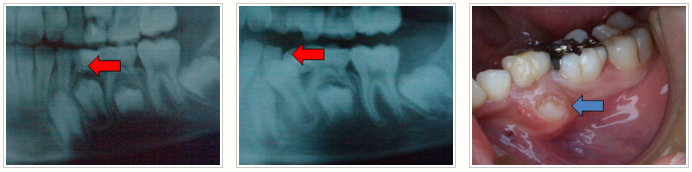

アゴの中のレントゲン

あごの成長不良

早く処置をしないと変なところから生えてきます。

4年生から6年生の奥歯の生え変わる時期は定期検診がとても大切です!

定期検診に来ないと変なところに生えてしまう…